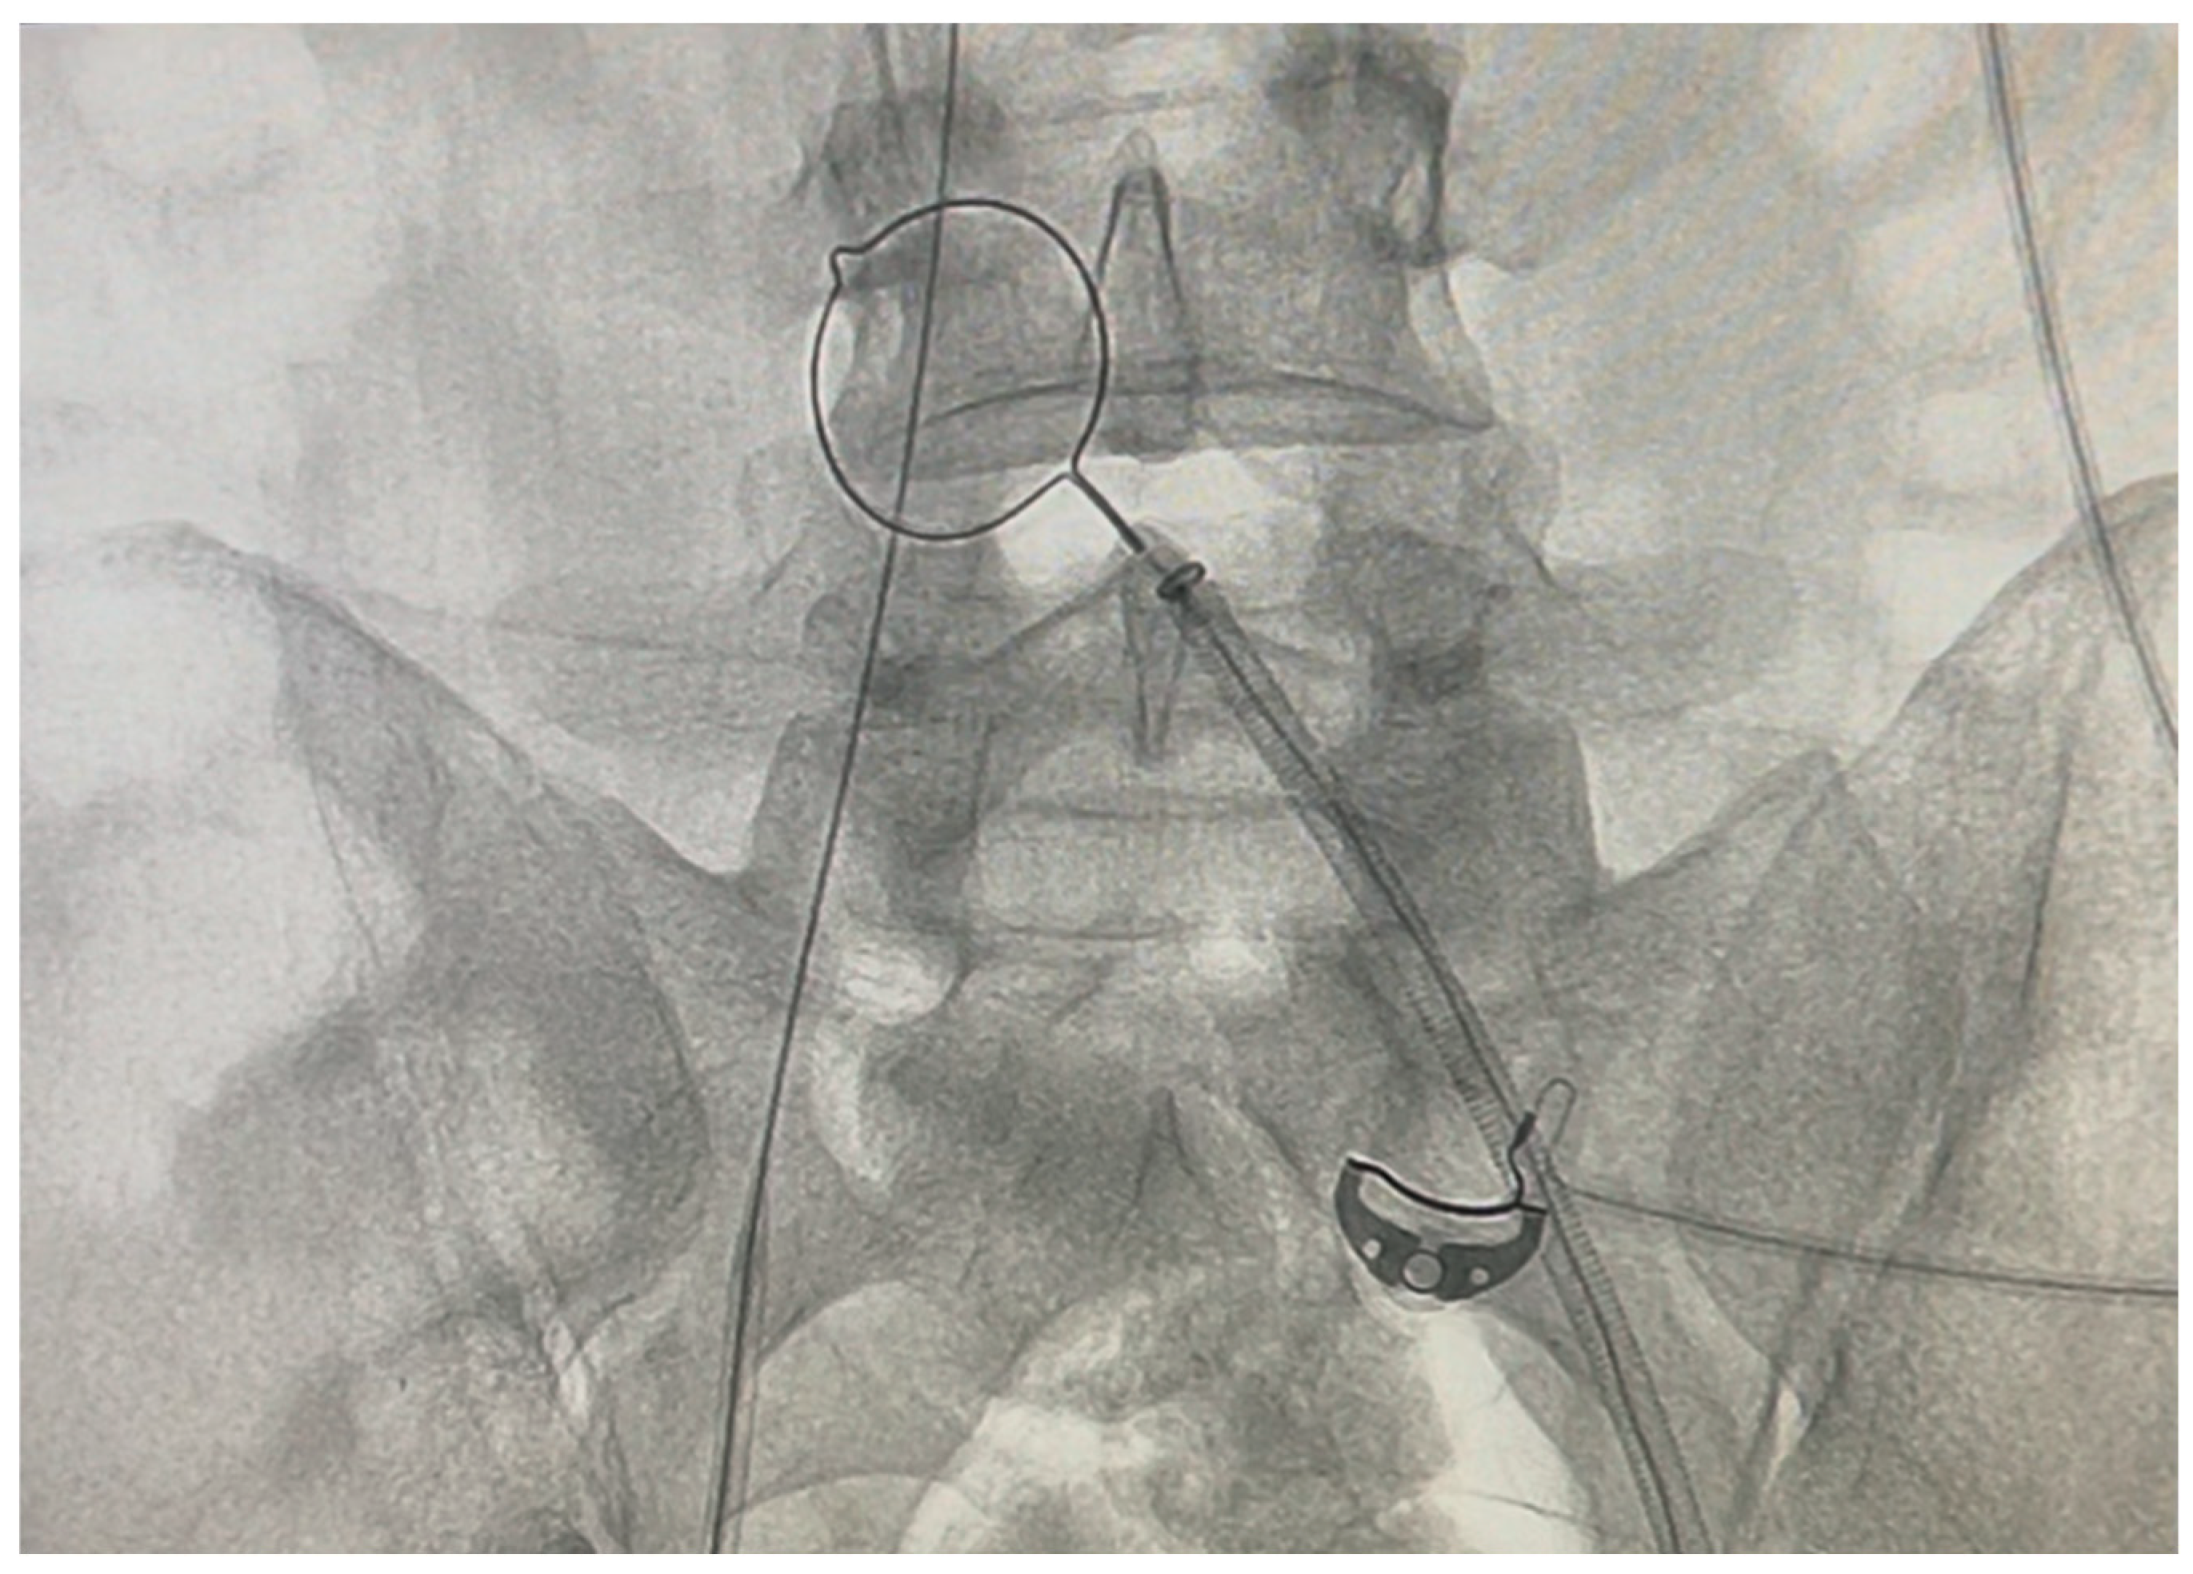

A Vascular Surgery consultation was ordered immediately by the attending BICU Plastic Surgeon and Intensivist. It was decided to transfer the patient to the Interventional Radiology department, where two interventional radiologists and the vascular surgeon attempted and accomplished the catheter removal. No findings of deep vein thrombosis or local signs of infection were evident. At first an effort was made to retract the catheter inserting a sheath as a dilator in the right femoral vein, without success. Under continuous angiographic visualization, catheterization of the contralateral (left) femoral vein was then performed using the Seldinger technique. A 0.035-inch soft wire was introduced as a diagnostic catheter. Once the end of the stuck catheter was located in the right iliac vein, a snare kit (Amplatz Goose neckTM Snare kit, ev3TM) was inserted and a 20-mm goose-neck snare was looped around the free end of the catheter and tightened to secure it. (Fig.3 and Fig.4) The catheter was then gently pulled out from the right femoral vein entry point. During the removal, a foreign body was seen (on the angiography screen) floating, assuming it being a piece of the broken balloon. Every effort should be made to prevent it from travelling up the inferior vena cava causing embolism. After unsuccessful attempts to catch it with the loop, it was transfixed on the vessel wall of left external iliac vein with a venous stent. The catheter was successfully removed. After the catheter removal, an Angio-Seal closure device was placed. On observation the middle balloon of the catheter (ICYTM has three balloons) was missing while the shaft of the catheter was intact. (Fig.5) The whole procedure in the radiology department lasted four hours.

Figure 4. Radiography during the catheter removal with the Snare Kit. .